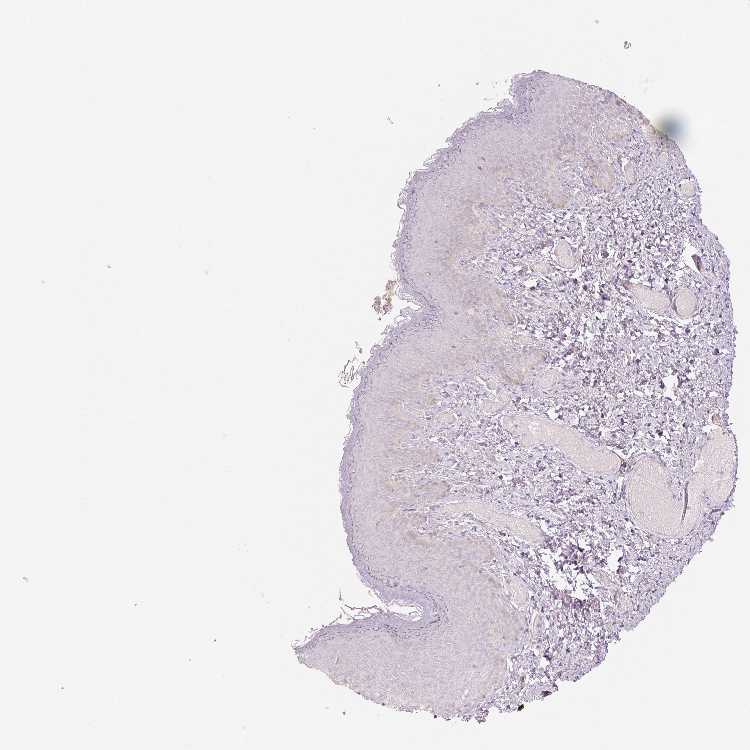

OR13C3